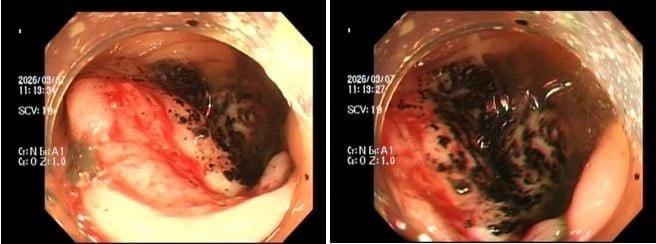

Qua thăm khám, sĩ phát hiện chị bị thiếu máu nặng. Ngay lập tức, chị được chỉ định nội soi đại tràng. Kết quả cho thấy chị có khối u lớn ở đại tràng, bề mặt loét và rất dễ chảy máu.

Tại bệnh viện, kết quả xét nghiệm cho thấy người bệnh thiếu máu nặng. Sau khi nội soi, phát hiện một khối u dạng vòng nhẫn đang chảy máu rỉ rả ở vùng trực tràng.